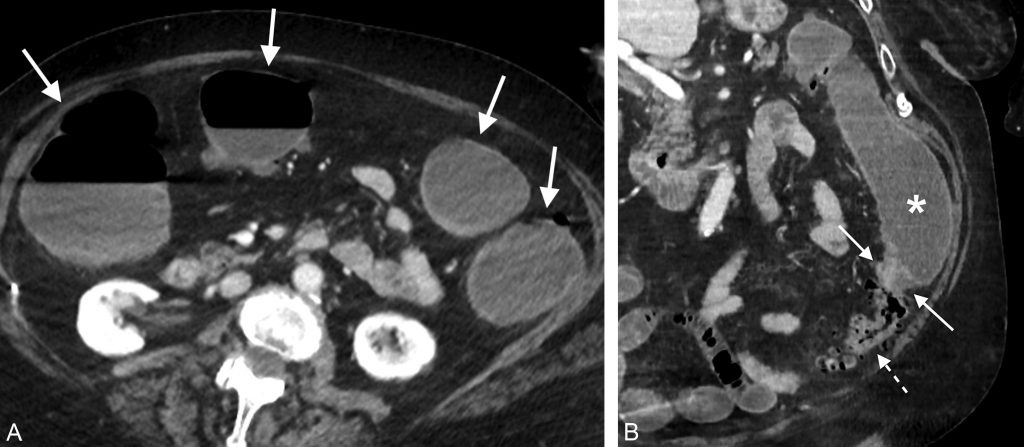

Si l’obstacle siège sur l’intestin grêle, les segments grêliques en amont de l’obstacle seront distendus et les segments grêliques d’aval ainsi que le côlon seront collabés ; les principales causes d’occlusion du grêle sont les brides et les adhérences. Si l’obstacle siège sur le côlon, alors tout l’intestion grêle ainsi que les segments coliques en amont de l’obstacle seront distendus et le côlon d’aval sera collabé (figure 14.2). Les principales causes d’occlusion colique sont les cancers et les volvulus coliques.

Fig. 14.2 Coupes tomodensitométriques après injection de produit de contraste iodé axiale (A) et coronale (B) d’une occlusion mécanique du côlon sur cancer colique gauche.

(A) Les segments coliques droit et gauche sont dilatés (flèches) avec un diamètre supérieur à 80 mm, signant la présence d’un syndrome occlusif du côlon. (B) L’obstacle est visualisé sur le côlon gauche sous la forme d’un épaississement pariétal court en faveur d’une sténose tumorale (flèches). Le côlon d’amont est dilaté (∗) et le côlon d’aval est plat (flèche pointillée). Noter la présence d’une diverticulose sur le côlon d’aval.

Source : CERF, CNEBMN, 2022.